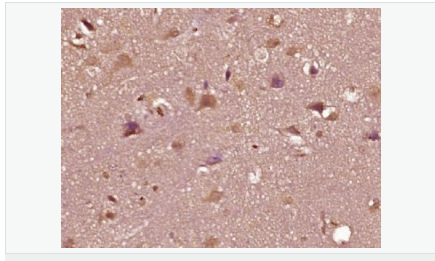

AR是一個(gè)由917個(gè)氨基酸組成的蛋白質(zhì),位于雄激素靶組織細(xì)胞中或細(xì)胞表面上的特異分子部位或結(jié)構(gòu)。 AR在前列腺癌中起著重要的作用,研究表明AR的表達(dá)與組織分型形成一定的相關(guān)性 ,AR在高分化的腫瘤中表達(dá)較多,而在低分化的腫瘤中表達(dá)較少。用于前列腺癌的檢測(cè),指導(dǎo)臨床治療,目前可用于乳腺癌、食道癌等各項(xiàng)腫瘤的研究。

image.png